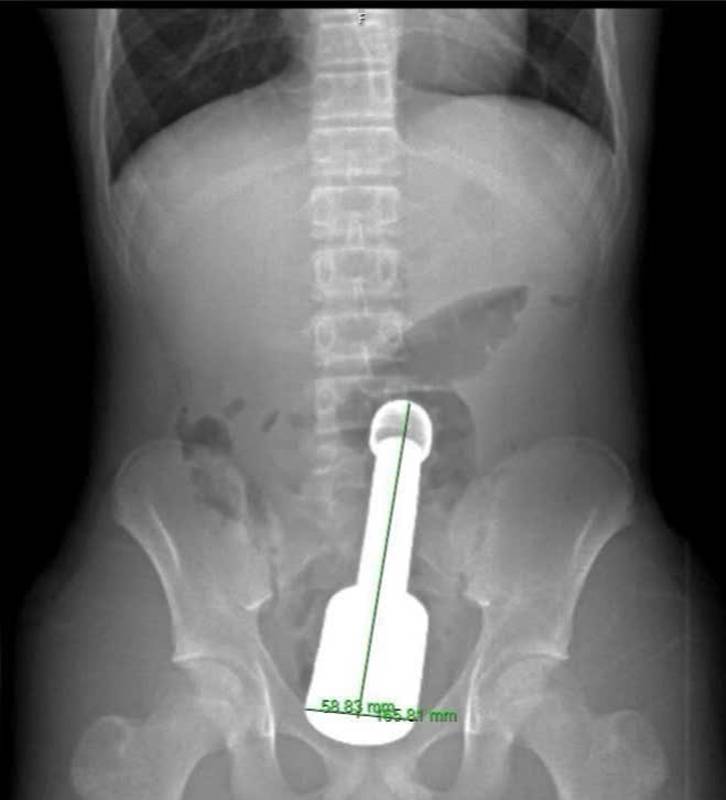

ภาพจาก Ha Dong General Hospital

วันที่ 10 มีนาคม 2569 โรงพยาบาลทั่วไปฮาดง ในกรุงฮานอย ของเวียดนาม มีรายงานเคสเด็กชายวัย 15 ปี ที่ถูกส่งมาโรงพยาบาลด้วยอาการปวดท้องช่วงล่างอย่างรุนแรง ผลจากการเอกซเรย์เผยให้เห็นวัตถุแปลกปลอมที่เป็นโลหะขนาดใหญ่ ติดอยู่ลึกเข้าไปในทวารหนัก จนเกิดการกดทับอุ้งเชิงกราน

ทั้งนี้ หลังจากใช้เวลากว่า 45 นาที ในที่สุดสากโลหะขนาดใหญ่ ยาว 18 เซนติเมตร เส้นผ่านศูนย์กลาง 6 เซนติเมตร ก็ถูกนำออกมาจากทวารหนักได้สำเร็จ โดยไม่ต้องผ่าเปิดช่องท้อง